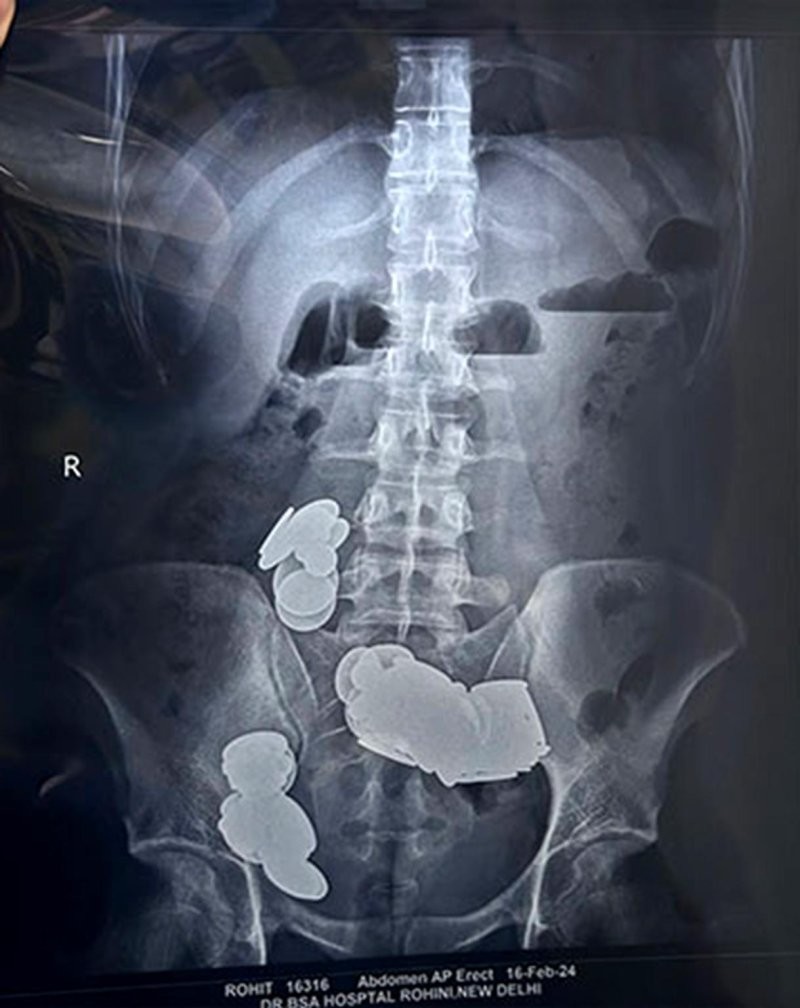

Рентгеновские снимки, сделанные перед операцией в больнице сэра Ганга Рама, показали, что в кишечнике образовались металлические сгустки. 26-летний атлет несколько недель "восполнял" дефицит цинка подручными средствами, когда проходил лечение от психиатрического заболевания, которое не раскрывается.

Пациент поступил в больницу с жалобами на боли в животе и рвоту, которые продолжались более 20 дней.

Монеты и магниты вызвали кишечную непроходимость, на стенках кишечника развилась эрозия. Мужчину экстренно прооперировали.

Извлечённые магниты имели форму сердца, сферы, пули, треугольника и звезды. Послеоперационный рентген подтвердил, что все инородные предметы удалены.